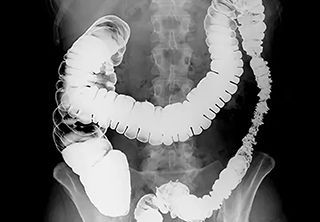

Ирригоскопия – это метод рентгенологического обследования толстой кишки. В качестве контрастного вещества чаще всего используются препараты бария. Они дают очень четкую рентгеновскую «тень», безвредны для организма пациента, а после исследования легко выводятся наружу.

Контрастное вещество, представляющее собой жидкую бариевую взвесь, вводится в прямую кишку с помощью клизмы. Этот процесс проходит под контролем рентгеноскопии. Во время заполнения кишечника контрастной смесью и в процессе опорожнения кишки специалист-рентгенолог выполняет прицельные и обзорные снимки. В некоторых случаях для лучшей визуализации может понадобиться дополнительное введение в толстую кишку некоторого объема воздуха. Все обследование занимает примерно полчаса.